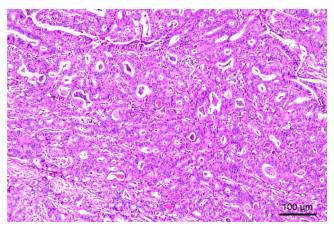

Construction of risk model of esophageal and gastric varices rebleeding in cirrhosis based on 2D-SWE

GUO Li, LOU Junge, YAN Yuanyuan

2025, 23(12): 2042-2045. doi: 10.16766/j.cnki.issn.1674-4152.004287

83 4

Abstract:

Objective  The pathophysiological mechanism of esophageal and gastric varices (EGV) rebleeding in liver cirrhosis is complex, and the mortality rate is high. Identifying the literature factors of EGV rebleeding is important to reduce the mortality rate. Two-dimensional shear wave elastography (2D-SWE) can evaluate the degree of liver hardness and pathological changes in a non-invasive and quantitative manner. This study discusses the construction of the EGV rebleeding risk model based on 2D-SWE to provide a reference for clinical prevention and treatment.  Methods  A total of 162 patients with EGV with cirrhosis admitted to Zhengzhou Central Hospital Affiliated to Zhengzhou University from January 2020 to December 2022 were selected. According to whether rebleeding occurred, the patients were divided into the no rebleeding group (127 cases) and the rebleeding group (35 cases). The risk factors of EGV rebleeding in patients with cirrhosis were analyzed by Logistic regression. To construct a nomogram prediction model for the EGV rebleeding in cirrhotic patients, and evaluate the prediction efficiency of the nomogram model.  Results  The proportion of Child-pugh grade A liver function, the proportion of mild esophageal and gastric varices and the level of ALB in the group without rebleeding were higher than those in the group with rebleeding (P < 0.05), and the proportion of first ligation, liver hardness and spleen hardness in the group with no rebleeding were lower than those in the group with rebleeding (P < 0.05). Logistic multivariate results showed that Child-Pugh grade of liver function, liver hardness, spleen hardness, and ALB were independent influencing factors for EGV rebleeding in cirrhosis (P < 0.05). A nomogram model for predicting EGV rebleeding in cirrhosis was established according to the logistic multi-factor results, and the model was verified. ROC curve analysis results showed that the C-index of the nomogram model was 0.903 (95% CI: 0.846-0.975), and the measured value of the nomogram model was basically consistent with the predicted value, with high predictive value and good clinical effectiveness.  Conclusion  2D-SWE detection of liver and spleen hardness is a risk factor for EGV rebleeding, and the prediction model based on this nomogram has a good predictive effect on EGV rebleeding.